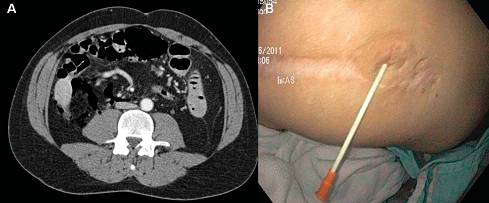

2. 使用金属夹或OTSC治疗瘘道

肠外瘘(ECF)的两端开口应该用不同方式治疗。为减少引流,需要关闭肠道开口,而皮肤端的开口需切开(图12),可在肠腔内使用导丝寻找瘘的外口(图13),ECF肠腔内的开口也可通过从皮肤开口处注射双氧水确定,而后在肠腔内通过金属夹夹闭肠内开口(图14),然而金属夹治疗瘘的效果受其抓取及固定炎性组织的厚度限制。

OTSC系统(“熊爪”)由施夹帽、抓取钳等部分组成,首先喷洒强力霉素溶液清洁瘘道,用细胞刷刮刷瘘道和开口处使瘘道去上皮化,然后以OTSC抓取钳抓取瘘管目标区域组织并用内镜吸入施夹帽,当抓取足够量的组织后即释放熊爪(图15)。已有文献报道OTSC可有效治疗胃皮瘘及其他消化道瘘,无并发症发生。我们也有用OTSC治疗回肠储袋-肛管吻合“J”漏顶端的成功经验。OTSC治疗CD瘘尚无文献报道,但此项技术已在我们中心进行,我们使用OTSC关闭ECF的肠内开口,我们认为它仅仅在较小的肠端开口处治疗有效,而皮肤端的开口需要用针刀或手术刀切开。另外需指出CD瘘的内镜治疗仅限于单一瘘管及较长的瘘道,疗效较好者一般见于直肠或储袋炎症程度得到最好控制的单纯肛周瘘,因此在内镜治疗前应该使用抗生素、抗炎药物及免疫调节剂、生物制剂等充分控制炎性。

图13. 内镜探查瘘道。 (A) 肠道内的瘘道开口。 (B) 以导丝进行探查。

图14. 内镜金属夹治疗瘘管。 (A) ECF皮肤开口 (B) ECF肠道开口 (绿色箭头). (C) 内镜喷洒双氧水确定瘘道。 (D) 在瘘道的开口处释放金属夹。